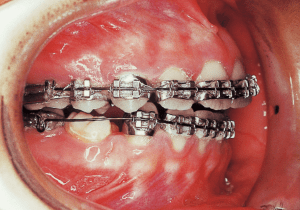

1 Initial Visit 9-2-’85

A transfer case where active treatment had been initiated at the previous orthodontist for 10 months (estimated, as no records were available at the time of transfer). The device is edgewise. The current occlusion exhibits a Class II molar relationship that is even stronger than the original state, and it has also become an open bite.